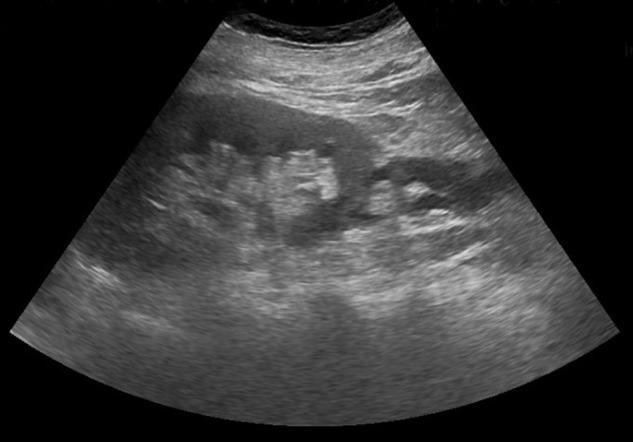

Non-traumatic ureteral rupture has been reported more frequently, resulting from increased intraluminal pressures from distal urinary tract obstruction. We report the case of a 77-year-old man presenting with chronic urinary retention secondary to massive prostatic enlargement through acute kidney injury. Ultrasound scan detected a shallow left perinephric fluid collection with a possible bladder mass, demonstrated on flexible cystoscopy to be a massive median lobe of prostate. Computed tomography confirmed extravasation of urine from the left proximal ureter. In the absence of specific symptoms, the patient had successful conservative management with antibiotics and urinary catheterization for his acute episode, although declined further surgical intervention.